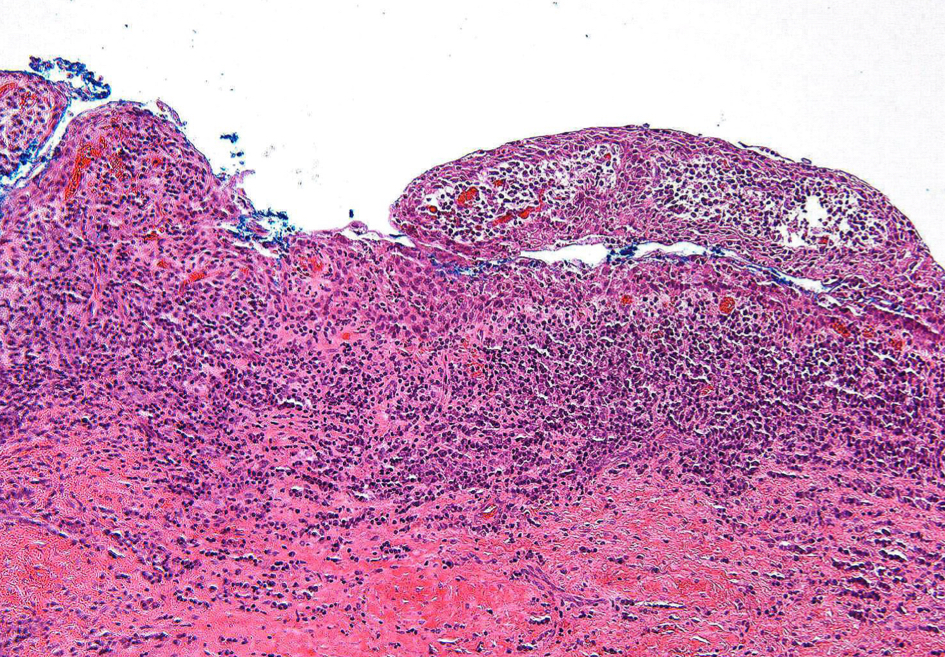

histopathological features:Â

lining of cyst composed of stratified squamous epitheliumÂ

wall of cysts consists of dense fibrous tissue w inflammatory infiltrate

periapical cyst

what gives rise to lining of a cyst?

epithelial rests